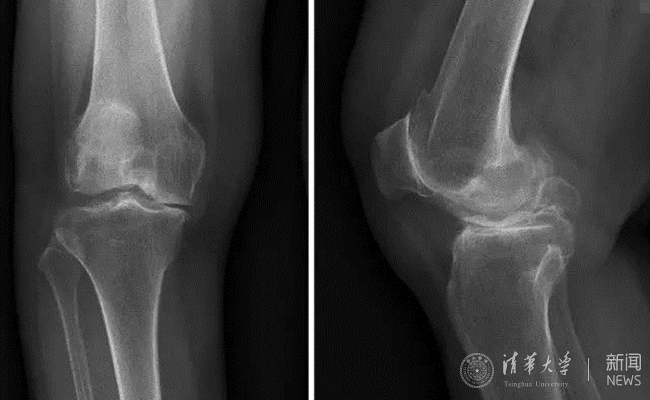

患者术前膝关节正侧位平片。